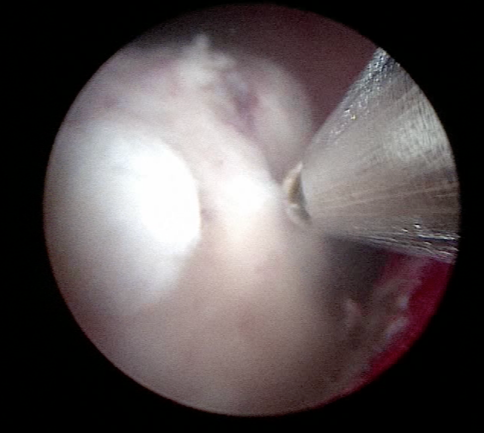

- το αδένωμα έχει πλέον αποκολληθεί από την προστατική κάψα και προωθείται στην ουροδόχο κύστη (εικόνες 5-6)

εικόνες 5-6